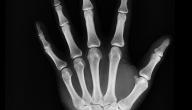

• اختبارات التصوير، يجرى فحص للمفصل بالأشعة السينية، أو الموجات فوق الصوتية، أو الرنين المغناطيسي، ومن خلاله يُشخّص وجود التهاب المفاصل.